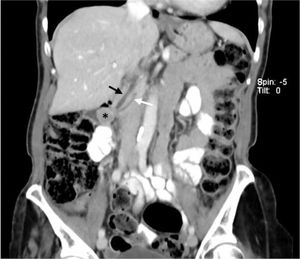

Se realiza un octreoscan, que no muestra evidencias de acumulación del radiotrazador que apunte a una tumoración con receptores de somatostatina. En la TC abdominal con contraste intravenoso se observa el nódulo de unos 17mm en la región periampular, que produce una mínima ectasia del colédoco y del Wirsung, y descarta la presencia de diseminación ganglionar o metástasis a distancia (fig. 1).